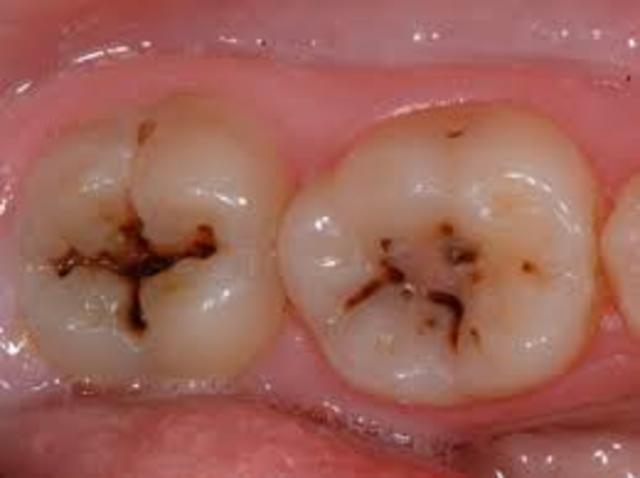

Muchos estudios clínicos han estudiado los mecanismos a través de los cuales las lesiones cariosas progresan y regresan con el objetivo de evaluar las estrategias dirigidas a la prevención de la caries dental.14 La capacidad de remineralización de las áreas desmineralizadas es uno de los factores que intervienen en los procesos que conducen a la caries dental.15

La caries dental resulta de la interacción de las fases de desmineralización y remineralización sobre esmalte cubierto por una placa produciendo ácidos.13